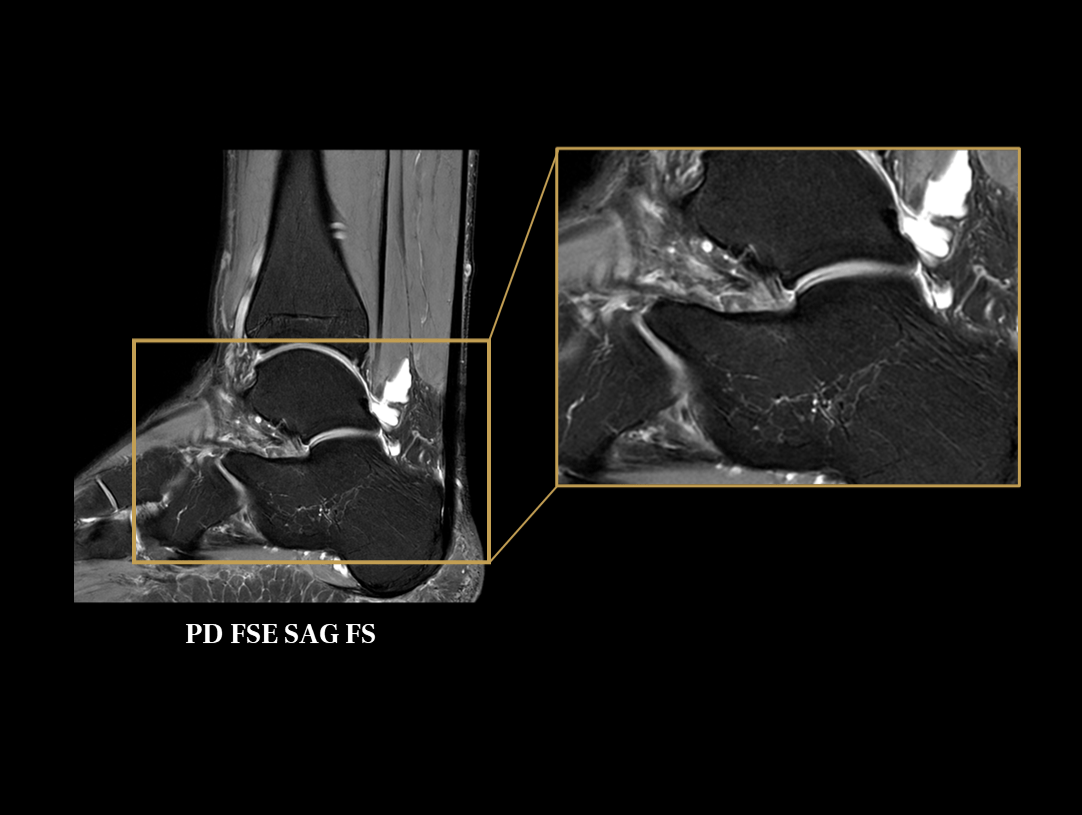

Galerie clinică

Gleznă